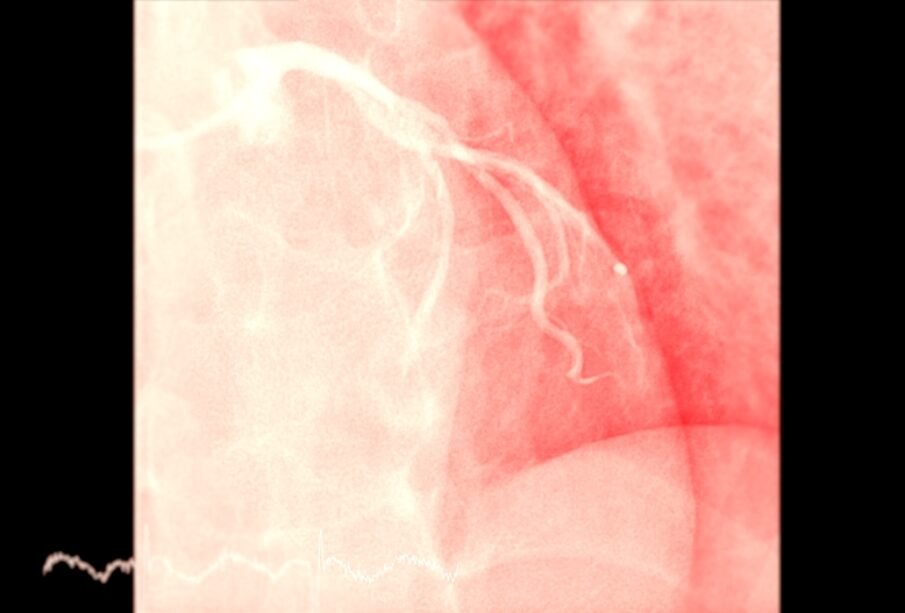

- Percutānā koronārā intervence (angioplastija ar stenta ievietošanu): sašaurinātajā artērijā ievada katetru ar baloniņu, ar kura palīdzību paplašina asinsvadu; pēc tam atstāj stentu, kas ir metālisks sieta veida balsts, lai uzturētu artēriju atvērtu.

- Stenta implantācija: stents ir plāna metāla caurulīte, ko ievieto artērijā, lai tā saglabātos atvērta.